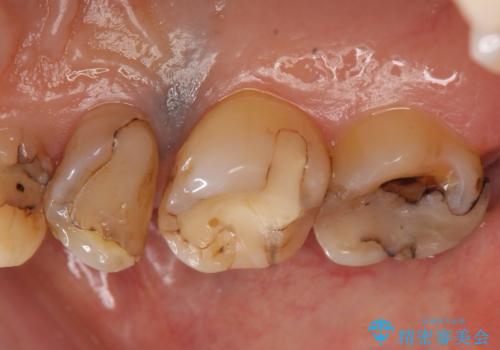

- 右上の奥歯がしみるので診て欲しいといらっしゃった方の症例です。

診査の結果痛みの原因は右上7番目だったため、古い樹脂と虫歯を除去後、オールセラミッククラウンによる補綴を行いました。

また右上5、6番目の歯も治療を希望されたため、オールセラミッククラウンによる補綴を行いました。